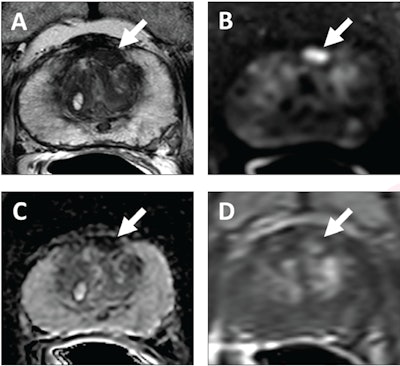

62-year-old patient with serum PSA level of 4.11 ng/mL. Prostate MRI shows lesion in left midanterior transition zone. Lesion (arrow) shows hypointensity on T2-weighted image (A), hyperintensity on high b-value DWI (B), hypointensity on ADC map (C), and focal early enhancement on dynamic contrast-enhanced image (D). Lesion was assessed as category 4 using PI-RADS version 2.1 MRI-targeted biopsy of lesion revealed prostate adenocarcinoma with ISUP grade group 2. At subsequent radical prostatectomy performed 6 months after biopsy, ISUP grade group was upgraded to 3. ISUP, International Society of Urogenital Pathology. Image courtesy of AJR.